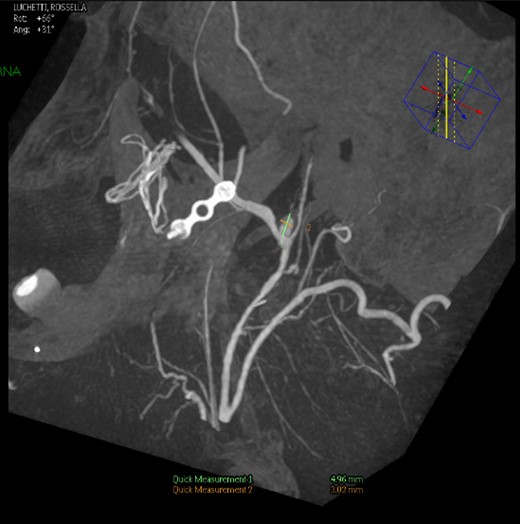

Intraoperative angiography was performed and revealed a PA in relation to the internal maxillary artery, ~1 cm posterior to the left subcondylar region (Fig. 2).

Left common carotid artery angiography in lateral views shows the PA (4.9 × 3 mm).

Under general anaesthesia, the right femoral artery was punctured and a guide catheter (5-Fr) was inserted. Selective runs were performed at the left common carotid artery and external carotid artery. The PA was detected at the bifurcation of superficial temporal artery and internal maxillary artery. Through a selective microcatheterization (1.7-Fr), coiling of the lesion and the bifurcation was performed. The final angiograms showed complete exclusion of the PA after coiling, with collateral flow networks that maintained distal patency of the proximally occluded vessels (Fig. 3).